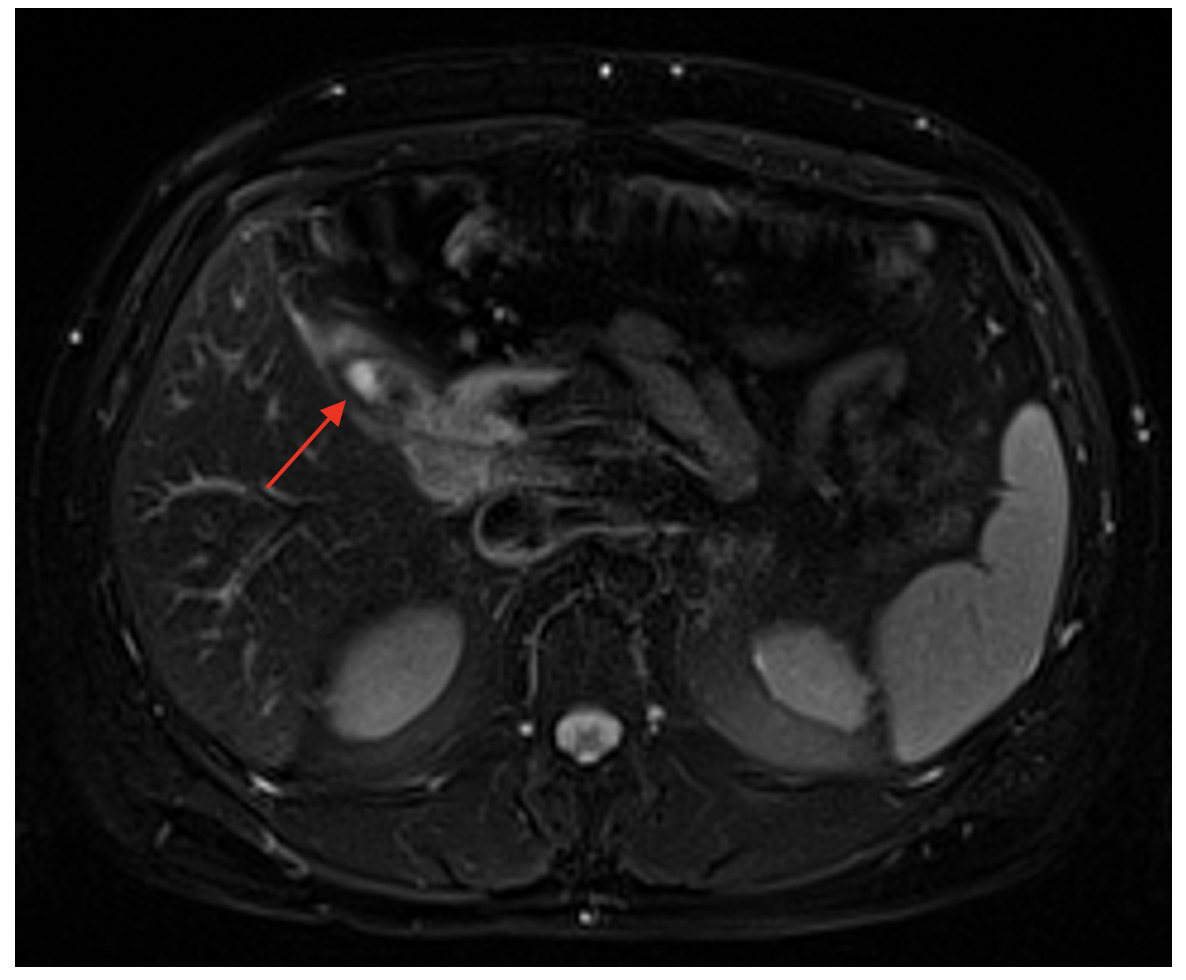

Initial computed tomography scan (CT) showed a thick-walled cystic structure containing stones in the gallbladder fossa which was indicative of chronic inflammation (Figure 1). Subsequent magnetic resonance cholangiopancreatography (MRCP) displayed evidence of a remnant gallbladder containing a 6-mm calculus (Figure 2). Patient was then scheduled for an elective robotic-assisted laparoscopic cholecystectomy for removal of the remnant gallbladder.

Physical examination and blood work narrow down the symptoms to hepatobiliary origin, but imaging allows for a definitive diagnosis to be made. If patients present to the emergency room, they may receive an abdominal CT scan as an initial study. This can display gallbladder dilation, gallbladder wall thickening, and radio-opaque stones.8,11,13 However, if cholecystitis is already suspected, an abdominal ultrasound may be used as a less expensive initial imaging study compared to CT scans. A study by Singh et al. demonstrated ultrasonography accurately identifying calculi in remnant gallbladders in 89% of their sample.14 However, in this study abdominal ultrasound failed to diagnose remnant gallbladder cholelithiasis in 11% of their patients. Similarly, Dikmen et al. displayed a failure to identify the remnant gallbladder in four (36.3%) of their eleven patients.12 The most definitive method of identifying the remnant gallbladder and surrounding anatomy is with an MRCP. In the study performed by Singh et al. MRCP was able to accurately diagnose remnant gallbladder calculi in all but two (4%) of the patients that underwent one.14 In our case, the patient presented to the emergency room initially, so he received a CT scan and an MRCP which led to the final diagnosis of remnant cholecystitis.